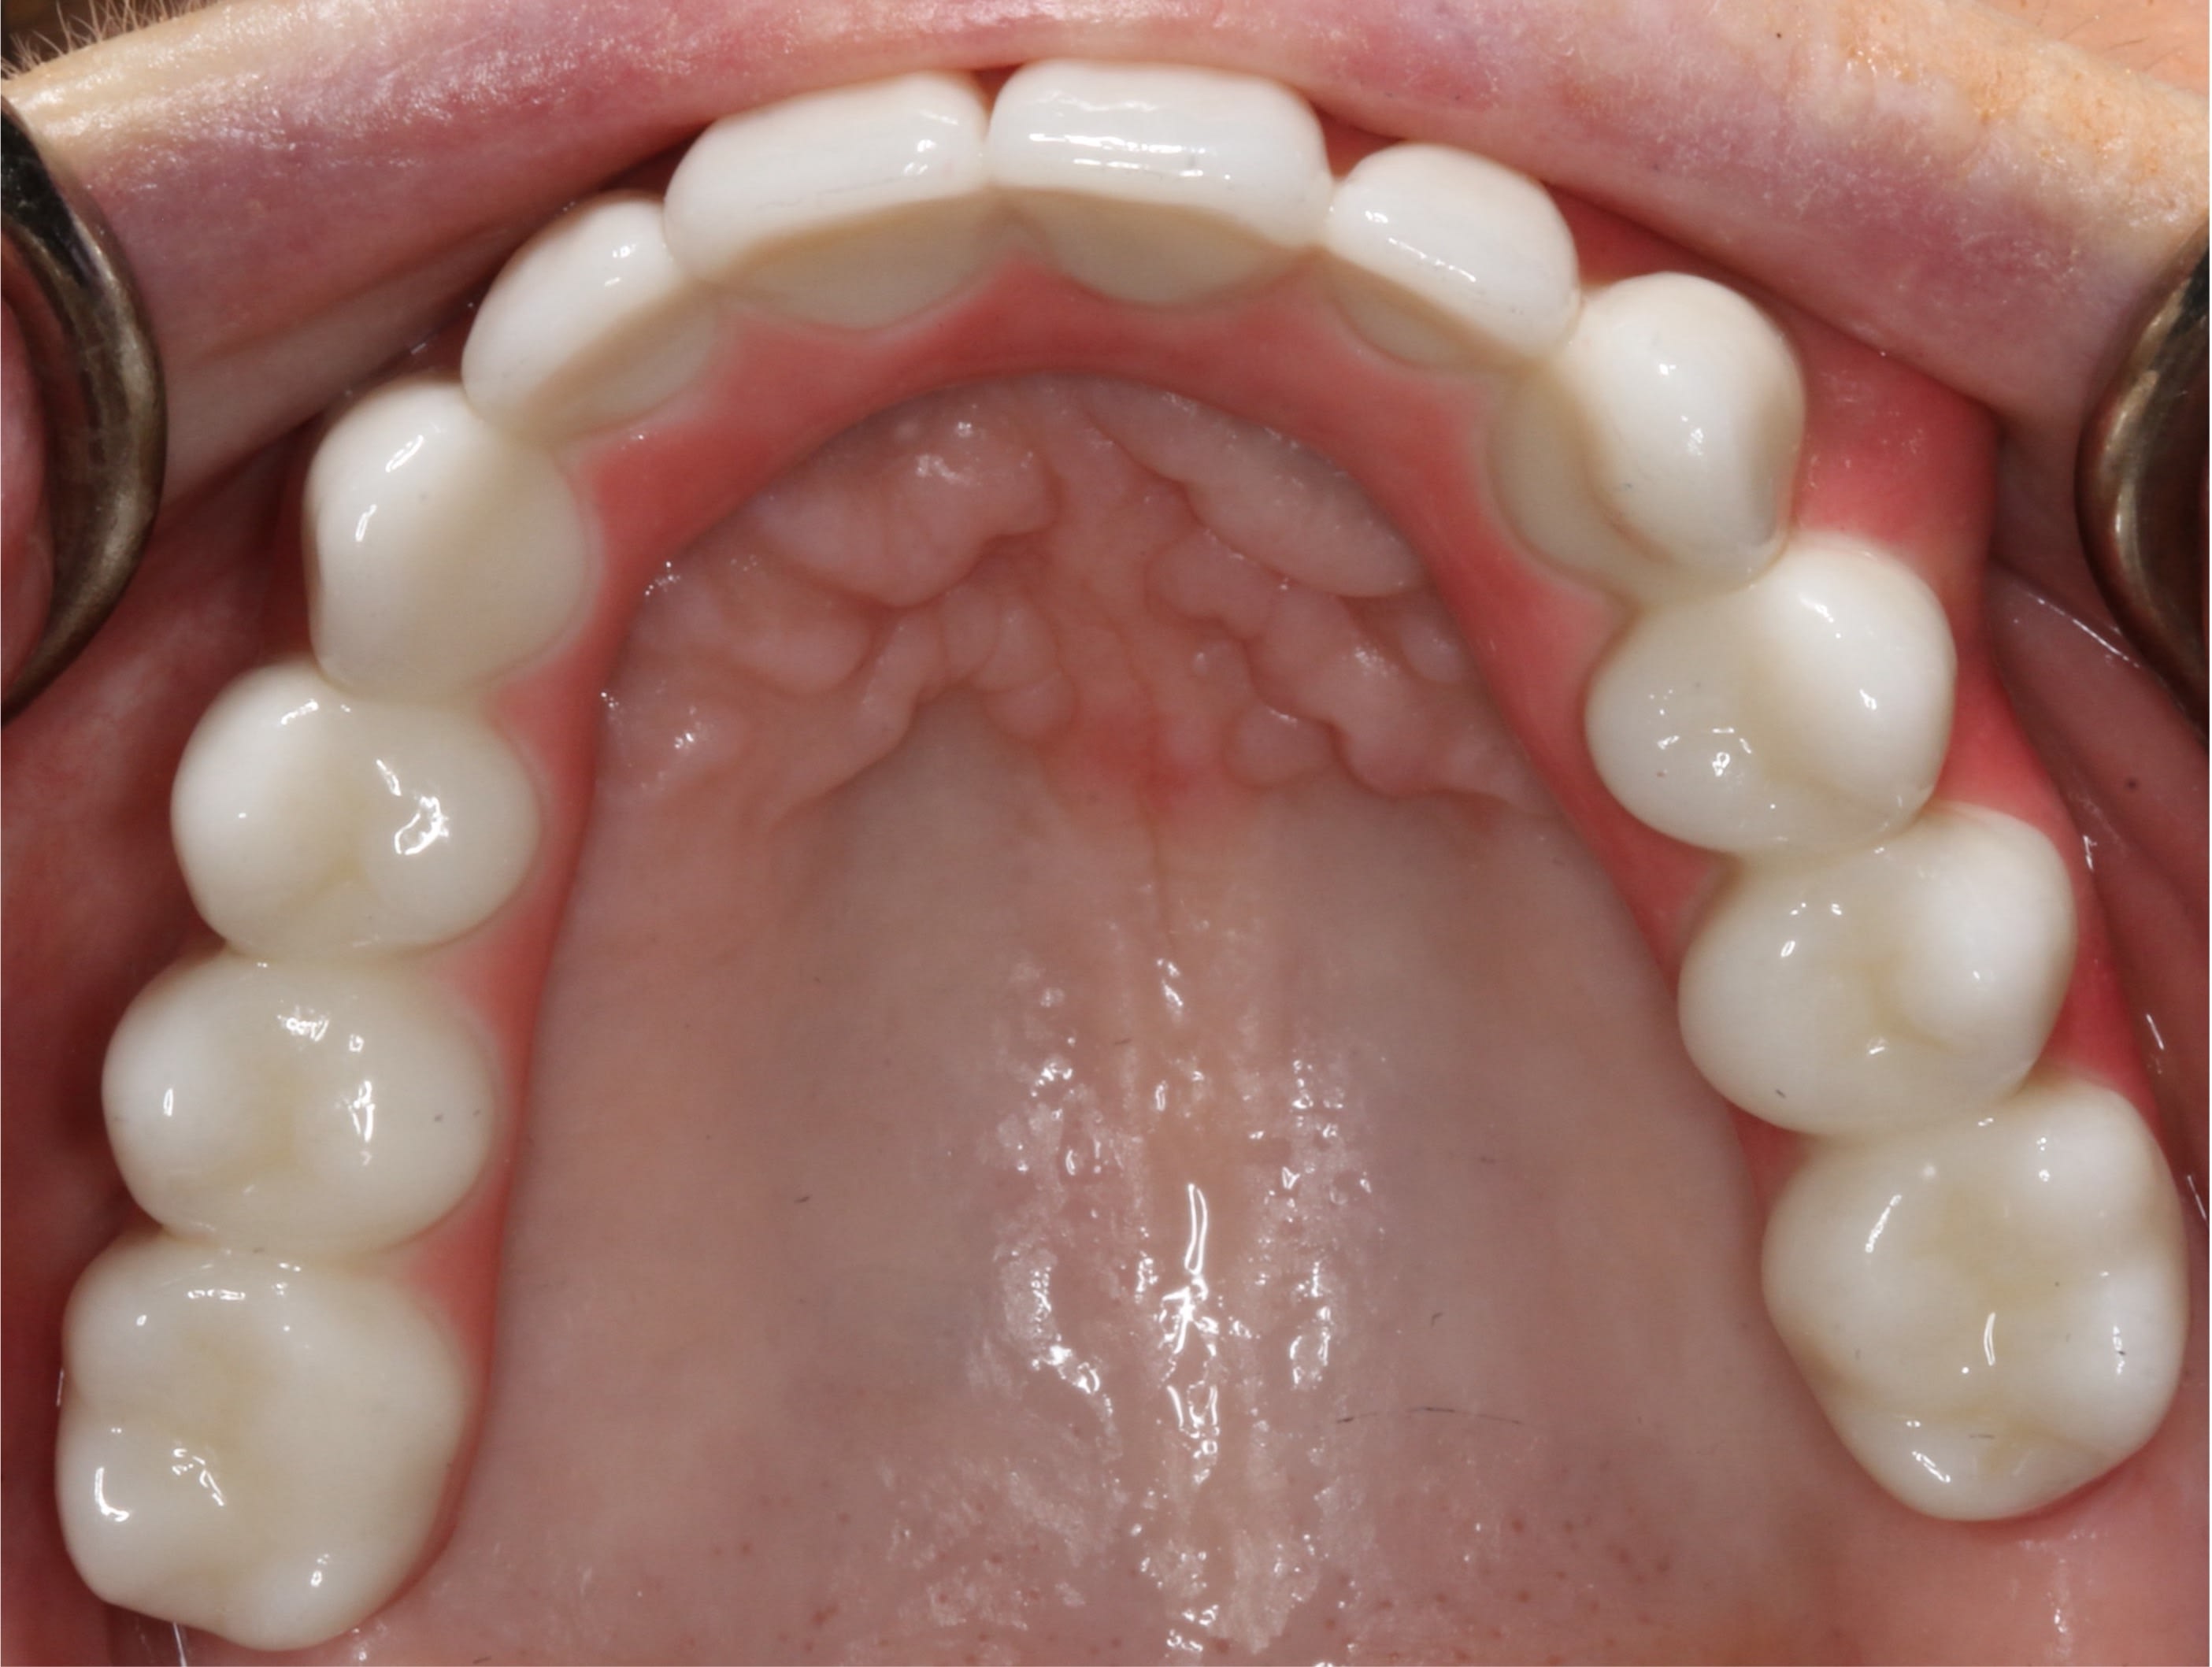

A polymethyl methacrylate (PMMA) appliance was verified for occlusion and esthetics (Figure 10). Once esthetics were evaluated and approved the final LOCATOR FIXED® prosthesis was processed in BruxZir zirconia (Glidewell). The black laboratory procession attachments were removed and replaced with the appropriate final LOCATOR FIXED® insert (Figure 11). The LOCATOR abutments and processing attachments are illustrated in Figure 12, which shows the tools for seating and removing the proprietary inserts and the insertion and removal tools. Proper inserts were selected and positioned per the manufacturer’s instructions (Figure 13). The final zirconia fixed prosthesis was seated using the seating tool and evaluated for stability (Figure 14). The prosthesis allowed for minimal palatal coverage, and the functional and esthetic maxillary reconstruction was complete (Figure 15 and Figure 16).

The patient was so pleased with the function, esthetics, and retention and the elimination of the palatal coverage that she requested a mandibular LOCATOR FIXED® restoration to replace the existing LOCATOR overdenture. Figure 17 illustrates the removal tool of this fixed prosthesis. The instrument engages under the bridge’s distal extensions for removal. Final CBCT analysis indicated acceptable integration of the dental implants supporting the fixed prosthesis (Figure 18).